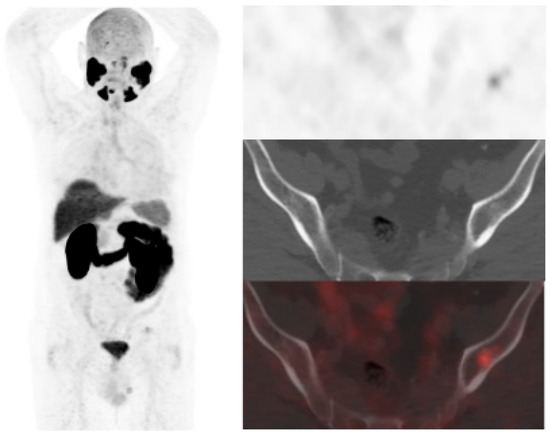

Derived from positive [18F]DCFPyL-PET/CT, 19 patients underwent additional diagnostic procedures to confirm the results: 8 by imaging (3/8 was confirmed) and 11 by histological analysis (8/11 was confirmed) (Figure 3 and Figure 4).

Figure 3.

55-year-old patient. Gleason 8 PCa treated with RP. First BCR treated with prostate fossa radiotherapy. Second BCR (PSA: 0.84 ng/mL, PSAdt 5.99 months, PSAvel 0.07 ng/mL/month). [18F]F-choline-PET/CT negative (a). [18F]DCFPyL-PET/CT (b), time window of twenty days, revealed two right external iliac lymph nodes metastases (white and yellow arrows). Lymphadenectomy was decided (escalation), without histopathological confirmation of malignancy. In follow-up, PSA progressed (2.07 ng/mL) and an additional [18F]DCFPyL-PET/CT (c) showed exactly same lymph nodes (white and yellow arrows). SBRT was administered decreasing the PSA level, reclassifying [18F]DCFPyL-PET/CT results as true positive.